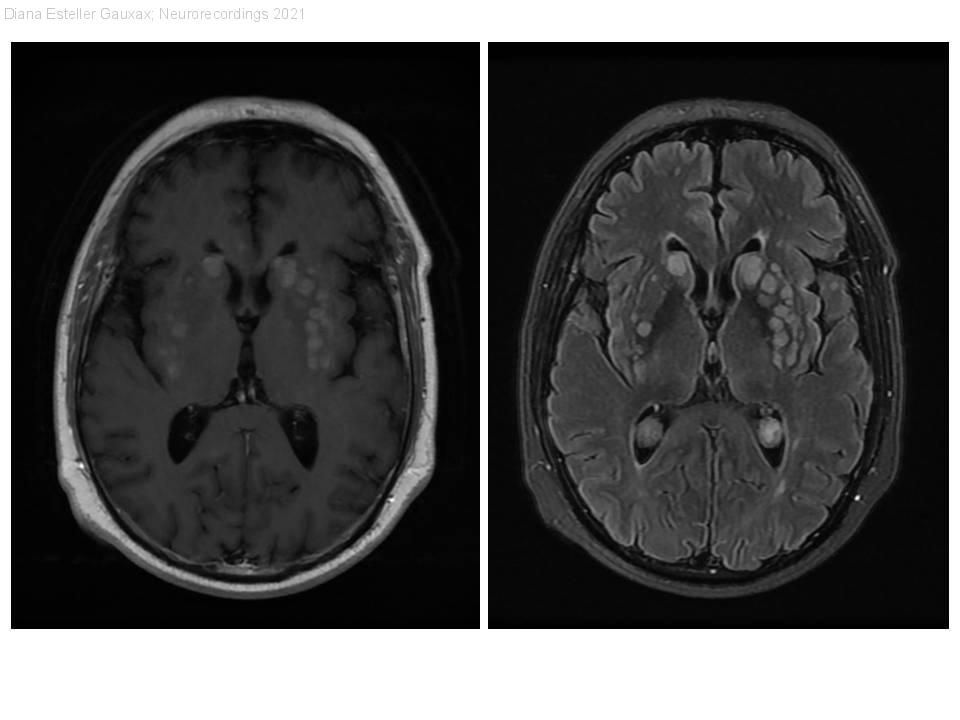

Síndrome medular secundario a metástasis miliares de carcinoma pulmonar de células pequeñas.

Diagnóstico final: Metástasis miliares cerebrales y medulares.

Resumen del caso

Paciente de 58 años, exfumador, con antecedente de cáncer microcítico de pulmón estadio IV A diagnosticado un año antes, tratado con quimioterapia (esquema CBDCA+VP16) e inmunoterapia (nintedanib) con enfermedad estable. Presenta paraparesia (4/5 proximal y...